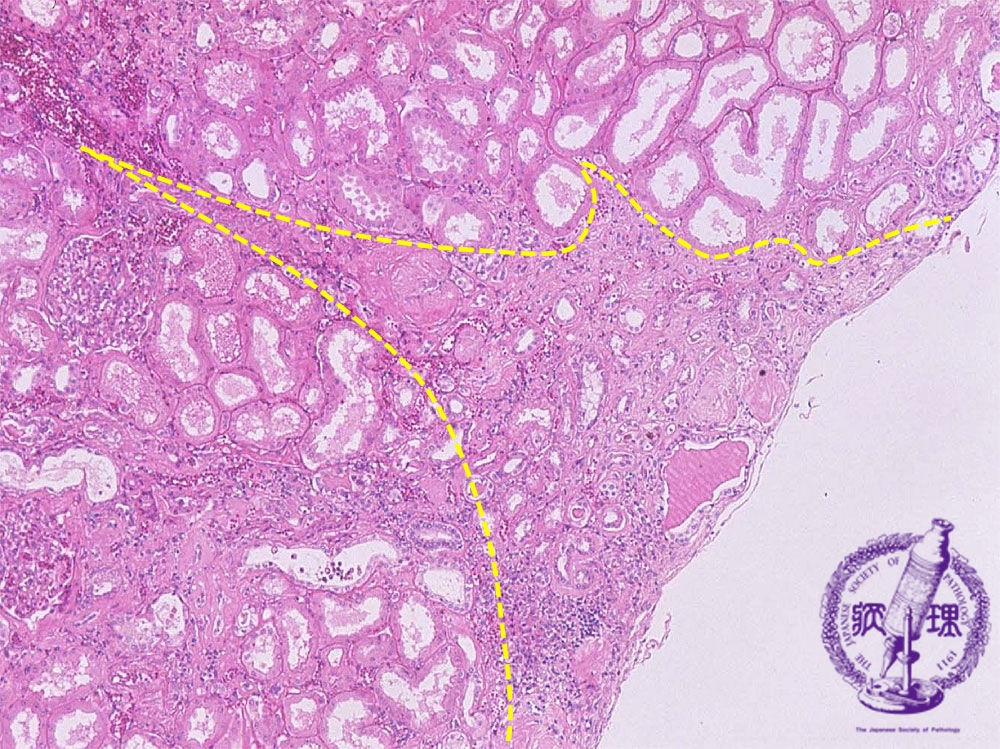

- ★(10)Nephrosclerosis(benign nephrosclerosis)

Microscopic image (HE, mid-power): The cortex shows wedge-shaped atrophy (yellow dotted line) with scar and a mononuclear cell infiltrate.